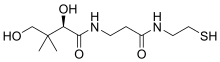

| Pantetheine | |

The disorder is caused by a mutant PANK2 gene located at the chromosomal locus: 20p13-p12.3. PANK2 is responsible for coding the protein Pantothenate kinase 2. PANK2 encodes the enzyme pantothenate kinase, and mutations in the gene lead to an inborn error of vitamin B5 (pantothenate) metabolism. Vitamin B5 is required for the production of coenzyme A in cells. Disruption of this enzyme affects energy and lipid metabolism and may lead to accumulation of potentially harmful compounds in the brain, including iron.

PANK2 encodes a 1.85Kb transcript which is derived from seven exons covering a total distance of approximately 3.5Mb of genomic DNA. The PANK2 gene also encodes a 50.5-kDaprotein that is a functional pantothenate kinase, an essential regulatory enzyme in coenzyme A (CoA) biosynthesis, and catalyzing the phosphorylation of pantothenate (vitamin B5), N-pantothenoyl-cysteine, and pantetheine (OMIM).

Phosphopantothenate has been shown to treat PKAN in a human, and also in a mouse model of the disease. Pantethine (a precursor of pantetheine) has been studied and shown to be effective in a mouse and in a fruit fly model of the disease.[9][10][11]